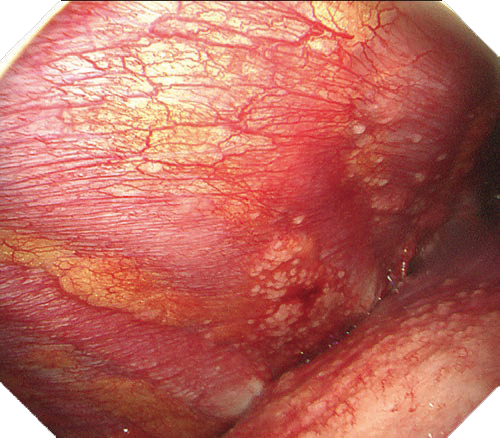

NBI

NBIは粘膜表層の血管走行が強調表示され、高精度な診断をサポートします。新しいスコープではより精細な血管構造の観察に貢献します。